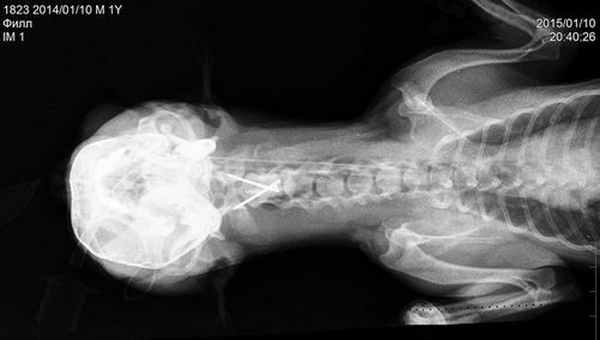

Рентген диагностика атлантоаксиальной нестабильности, в плане принятия решения о проведении хирургической ее коррекции, не информативна и в нашей клинике не проводится. Наиболее полное представление о степени выраженности данной патологии, так же как и о наличии сопутствующих изменений в нервной системе, можно получить только на основании данных нейровизуальных исследований, таких как МРТ или КТ- томографии.

Применение нативного кт позволяет получить надежные доказательства (является методом выбора) наличия атланто-аксиальной нестабильности и оверлеппинга однако следует помнить, что последний может быть динамическим и меняться при определенных положениях головы.

Построение мультипланарных реконструкций на КТ особенно помогает при оценке типа повреждения и используется для получения дополнительных данных для хирургического лечения, а именно пространственных соотношений позвоночного канала, степень зрелости скелета, объем боковых масс атланта, объем и степень атрофии костей черепа. И поэтому по нашему убеждению – является ОБЯЗАТЕЛЬНЫМ! Они как и трехмерные реконструкции поверхностей полезны для планирования хирургических операций на позвоночнике.

Краниография собаки с вентральной стабилизацией С1-С2.

Интраоперационное - вентральная фиксация спицами Киршнера первого и второго шейного позвонка.